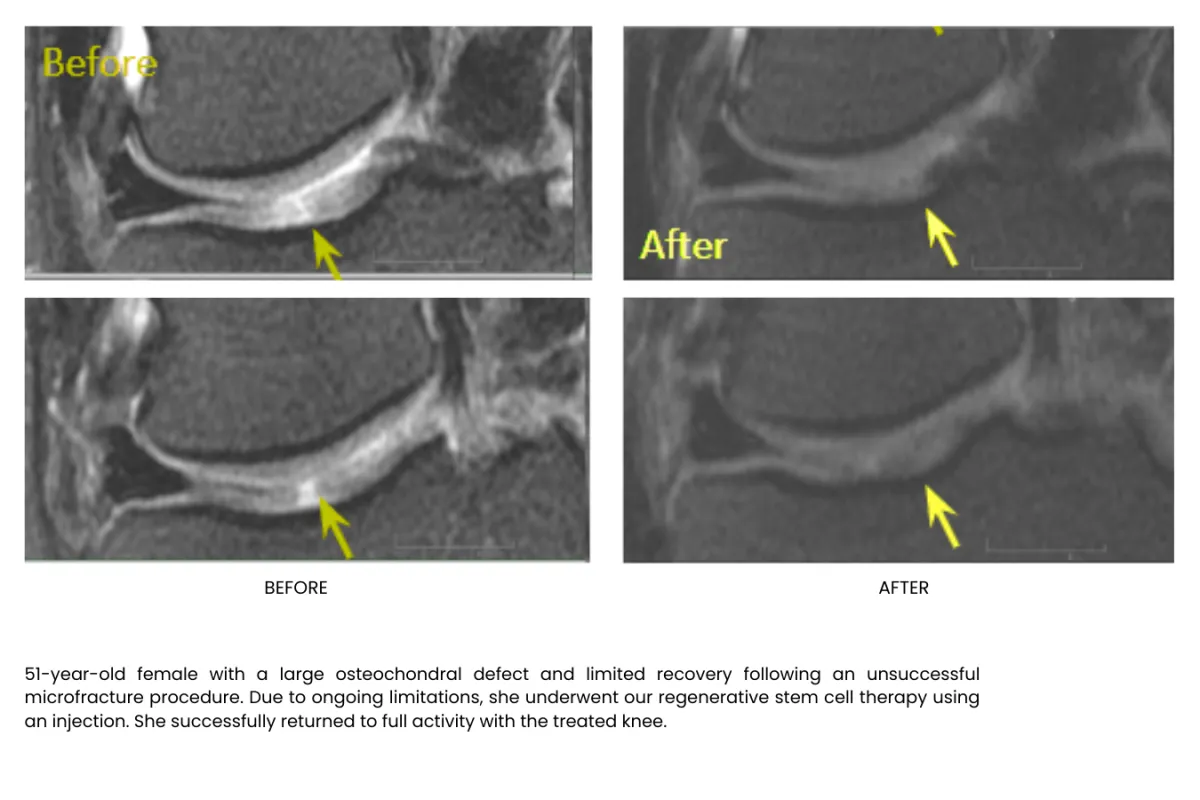

Millions of stem cells delivered precisely in the injured area building up tissue, recovering and freeing your from pain, without surgery or long recoveries.